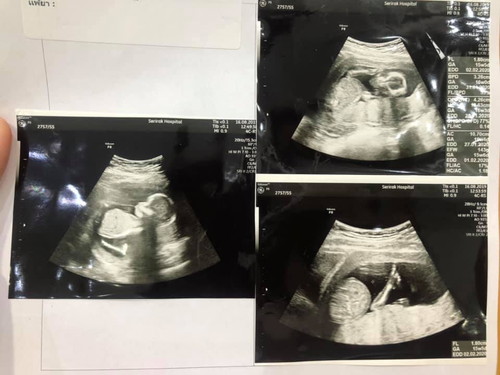

ลุ้นเพศลูกน้อยคะ

เพิ่งไปซาวน์มาตอน 16 วีคคะ แต่หมอยังไม่บอกเพศเลยจ้า ตอนนี้กำลังลุ้น ตื่นเต้นมากคะ คุณแม่ว่า ผญ / ผช คะ

เหมือนผช เลยค่ะ